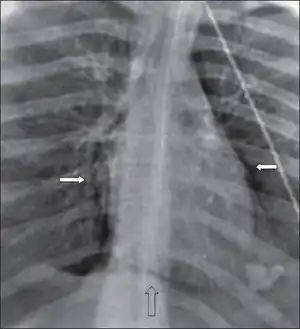

| CT scan showing pneumopericardium with pneumomediastinum, pneumothorax, hemothorax, and pulmonary contusion after severe chest trauma[1] | |